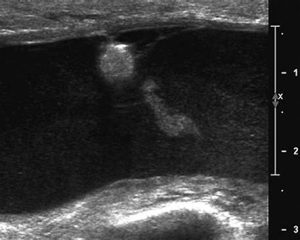

4. Caracterización de la colección

Evaluar:

• Contenido anecoico vs heterogéneo

• Bordes definidos

• Septos

• Forma

6. Doppler obligatorio si hay duda

Seroma simple = sin flujo interno.

Si existe flujo interno o hiperemia marcada, reconsiderar diagnóstico.